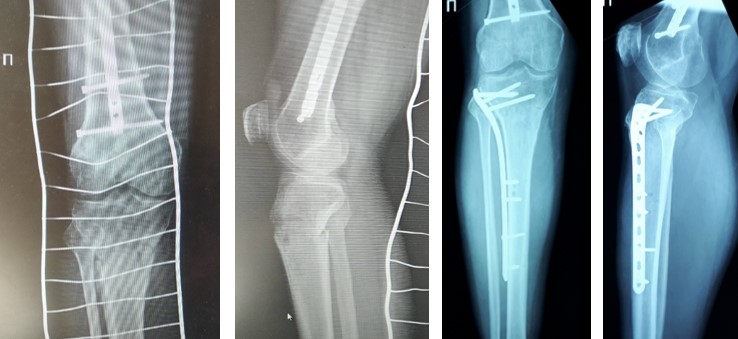

Відкрита репозиція та внутрішня фіксація залишається золотим стандартом лікування. Використовують різні хірургічні доступи залежно від локалізації перелому. Фіксацію здійснюють кутовими пластинами з кутовою стабільністю, гвинтами, спонгіозними гвинтами з шайбами. При наявності кісткового дефекту виконують кісткову пластику.

Черезшкірна фіксація застосовується при простих переломах без значного зміщення, дозволяє зберегти кровопостачання кісткових фрагментів та мінімізувати пошкодження й без того травмованих тканин.

Біологічний остеосинтез передбачає мінімальну травматизацію м'яких тканин, збереження кровопостачання кісткових фрагментів, використання малоінвазивних доступів та сучасних фіксаторів.